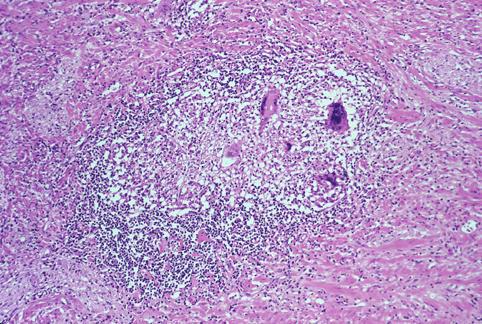

Tuberculosis of the ileocecal region which required an operation due to severe stenosis.

Inflammatory or ulcerative disease / lesions/tuberculosis

Large intestine(Colon)/Ilenocecal region

Histology